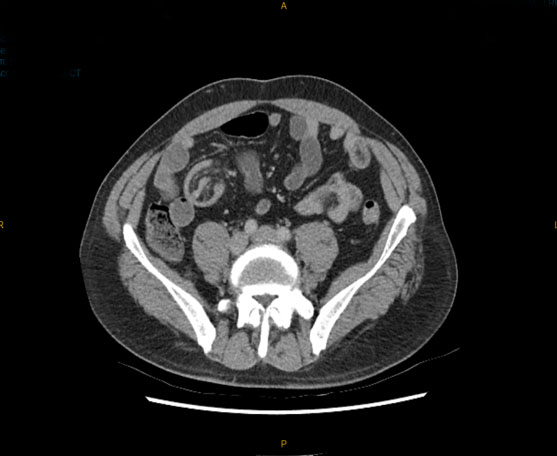

Jejunal diverticulosis (JD) is an uncommon and often underdiagnosed condition, usually discovered incidentally and rarely associated with acute complications such as diverticulitis, obstruction, abscess, perforation, or fistula formation. However, when complications do occur, they can be severe and diagnostically challenging. We present the case of a 75-year-old Female who arrived with an acute-onset abdominal pain with progressive distension and persistent vomiting. Computed tomography (CT) revealed a small bowel obstruction due to an enterolith. Emergency laparotomy revealed a small bowel obstruction at mid ileum due to an enterolith as well as an omental band adhered to the inflamed jejunal diverticulum proximally resulting in a closed loop in the affected segment of small bowel. The omental band was divided and the enterolith was removed via an enterotomy without requiring a small bowel resection. The patient was managed with antibiotics postoperatively and she made an unremarkable recovery. Closed loop small bowel obstruction as a result of complicated jejunal diverticular disease is rare in the literature and it highlights the critical importance of maintaining a high index of suspicion, particularly in older patients presenting with acute abdomen.